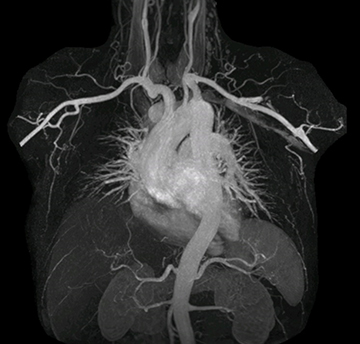

The subtractionless peripheral MR angiography shows improved vessel-to-background contrast and high resolution. Ingenia Ambition 1.5T.

“Before we had Ingenia Ambition, our CE-MRA run-off studies would first acquire a dynamic pre-contrast scan with 20-25-second breath-holds, then inject the contrast, do another acquisition and then subtract the two,” says Avila. “Now, mDIXON XD allows us to complete the study in just one single pass – without need for a pre-exam – which eliminates subtraction artifacts and almost halves the scan time. In addition, mDIXON provides much better background suppression, which really improves vesselto-background contrast. And, thanks to Compressed SENSE, the single breath-hold is not long and we improve image resolution.”

Performed on Ingenia Ambition. FOV 430 mm, voxels 1.3 x 1.3 x3.0 mm, 130 slices, Breath hold 16.6 sec

Using mDIXON provides excellent fat saturation uniformity. No artifacts seen at the edges in these images, while these were quite commonly seen with eTHRIVE on our previous system. Note also the high resolution.

Ingenia Ambition, 3D breath hold, FOV 370 mm, voxels 1.51 x 1.58 x 4.0 mm, 120 slices, scan time 19.6 sec.